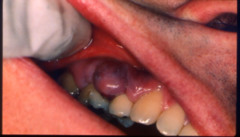

ranula

-fluid filled swelling that increase and decreases in size floor of the mouth -larger than mucocele